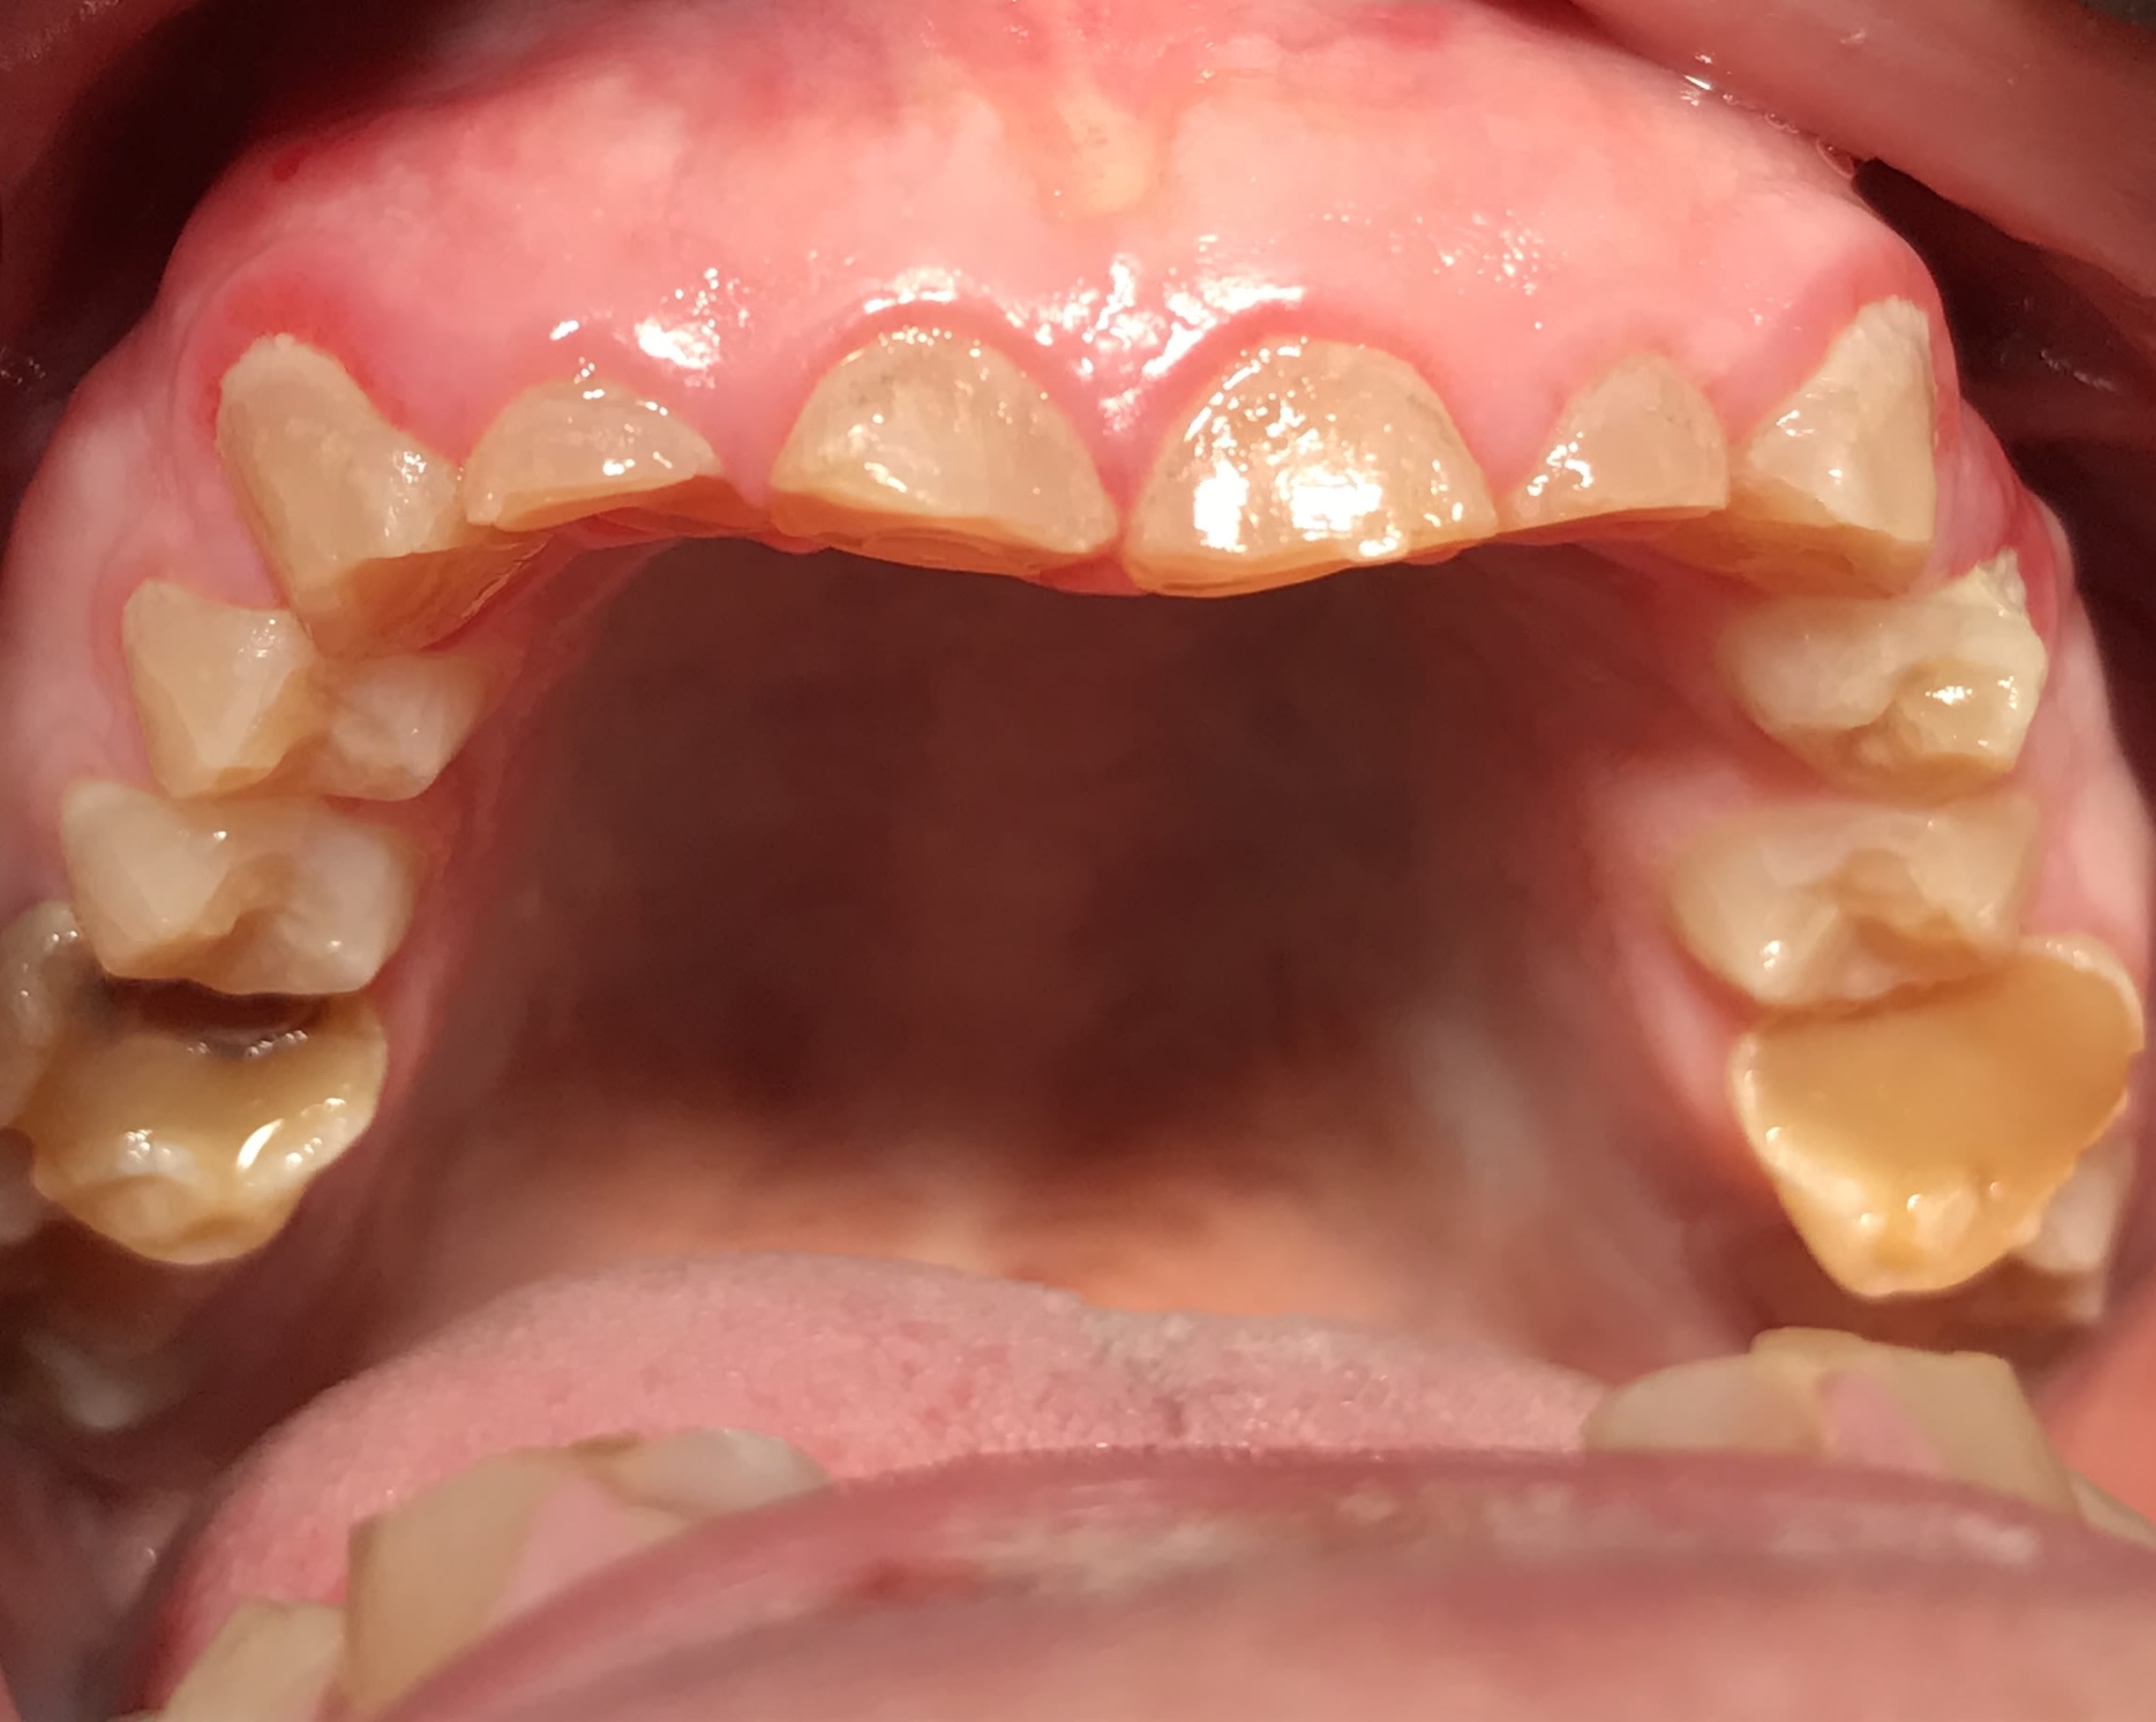

Photos

A82f03fd 2d91 4ef1 97ca f3eb47c7b10d m438gf - Eugenol

780581f7 855e 4bfa 8613 66d779c84307 rrwohx - Eugenol

poignée de porte a diagnostiqué une maladie genetique, c'est un cas d'amélogenèse imparfaite avec racines courtes, obliteration des chambres pulpaires, émail fin et de mauvaise minéralité pour du collage... necrose en lien avec l'usure (les incisives inf)

Oui Mla2 problème génétique + bruxisme. Quand vous expliquiez qu’il était camé moi je veux bien mais bon regardez ses 6 . Ses prémolaires sont quasi intacts . Ils se seraient foutus de l’acide juste sur ses incisives et ses molaires .... étrange. :)

L'amélogénese imparfaite, toutes les dents sont touchées à égalité; et l'émail a un aspect visuellement altéré.